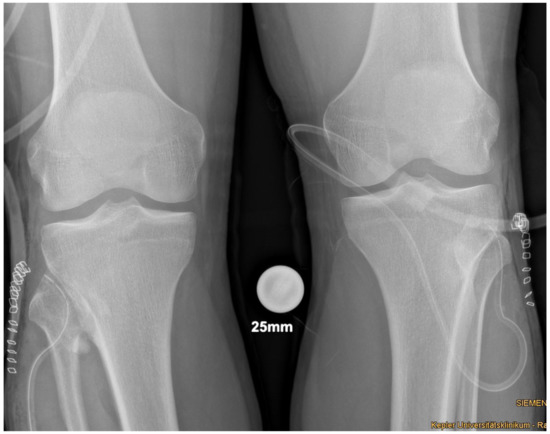

Plain radiographs, performed in anterior-posterior and lateral views of both knees showed a bony excrescence originating from the lateral tibial condyle as well as from the head of the fibula (Figure 1). The joint space was hardly visible. There were no signs of fracture or osteolysis.

Figure 1. Plain radiograph in a.-p. view showing the bilateral synostosis.